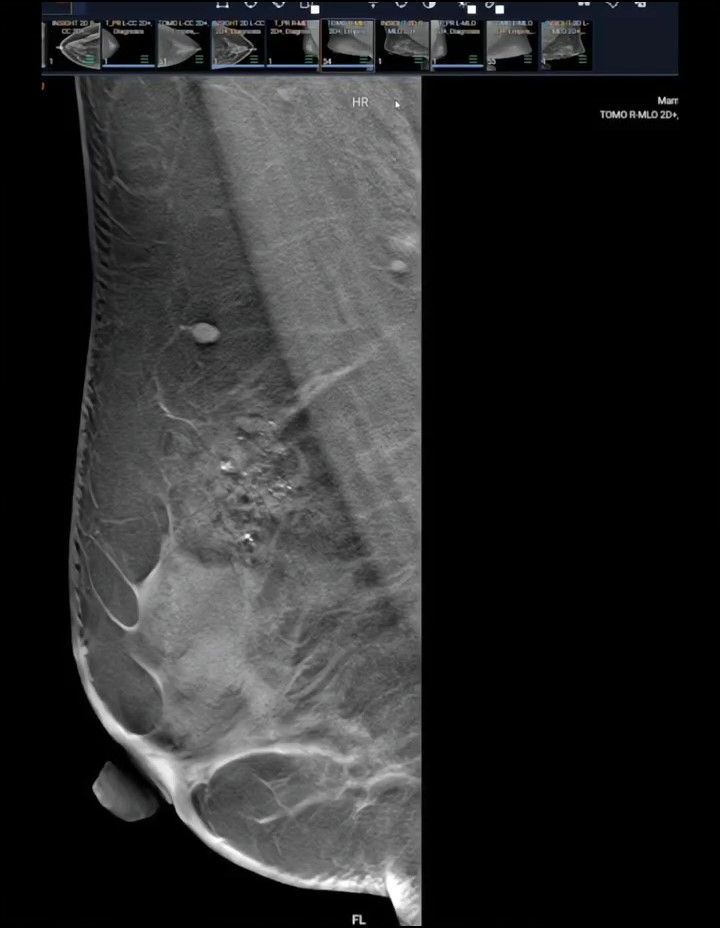

Sau khi siêu âm tuyến vú, bác sĩ chỉ vào màn hình và bảo tôi: "Đây là u xơ tuyến vú nhỏ, rất may em đi khám kịp lúc. Chỉ cần theo dõi định kỳ, chưa cần làm gì".

Mammocare là trung tâm chuyên khoa tuyến vú với đội ngũ bác sĩ giàu kinh nghiệm, thiết bị hiện đại và quy trình nhẹ nhàng, tế nhị.